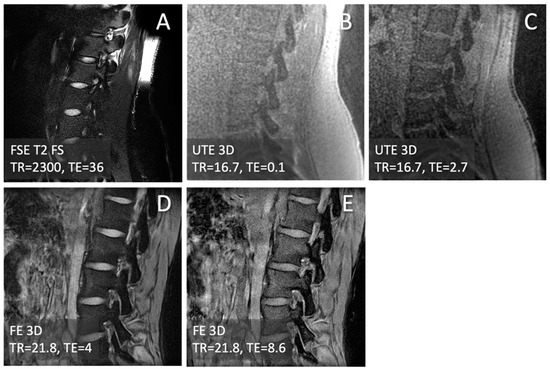

2.3. CT-like Image Processing

3.1. Observations